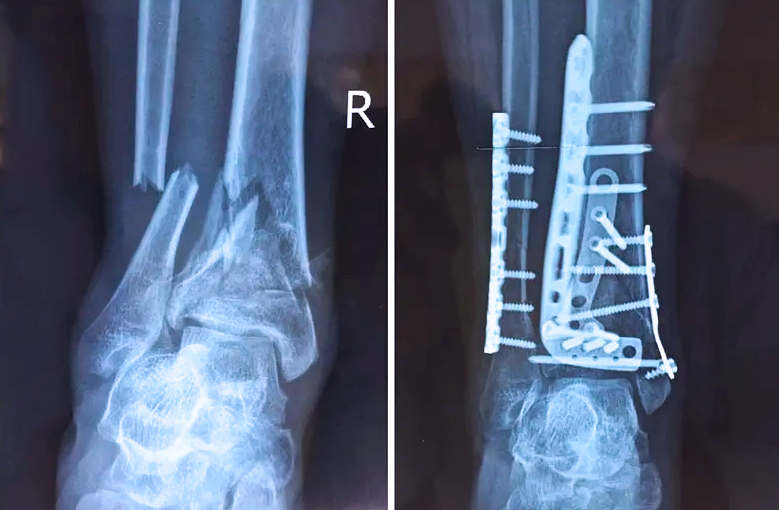

對于骨科醫(yī)生而言,關(guān)節(jié)外的骨折是相對比較簡單的,因為關(guān)節(jié)外的骨折允許我們復(fù)位的時候有一些偏差,但是如果骨折部位在關(guān)節(jié)內(nèi),我們就不能有任何的偏差。而且關(guān)節(jié)內(nèi)的骨折是有關(guān)節(jié)面的,如果關(guān)節(jié)面不平整,就會導(dǎo)致患者以后出現(xiàn)創(chuàng)傷性關(guān)節(jié)炎等癥狀,或者出現(xiàn)長期的疼痛,甚至造成殘疾。所以對于關(guān)節(jié)內(nèi)的骨折,一定要做到“解剖復(fù)位”,就像搭積木一樣,每個積木塊、每個碎骨塊都要完好的拼到一起,做到嚴(yán)絲合縫。

踝關(guān)節(jié)是人體中負(fù)重較大的關(guān)節(jié),也是活動度較大的地方,所以對于足踝部位的關(guān)節(jié)內(nèi)骨折,我們更需要做到“解剖復(fù)位”。對于這種關(guān)節(jié)內(nèi)的骨折,尤其是踝關(guān)節(jié)內(nèi)部的骨折,不僅需要進行X影像平片正側(cè)位的拍攝,由于在二維影像上無法判斷關(guān)節(jié)面的受損情況,往往還需要進行三維影像的檢查。

在術(shù)前,我們需要做三維掃描的CT檢查,我們必須要有CT的片子,還要有三維的重建。